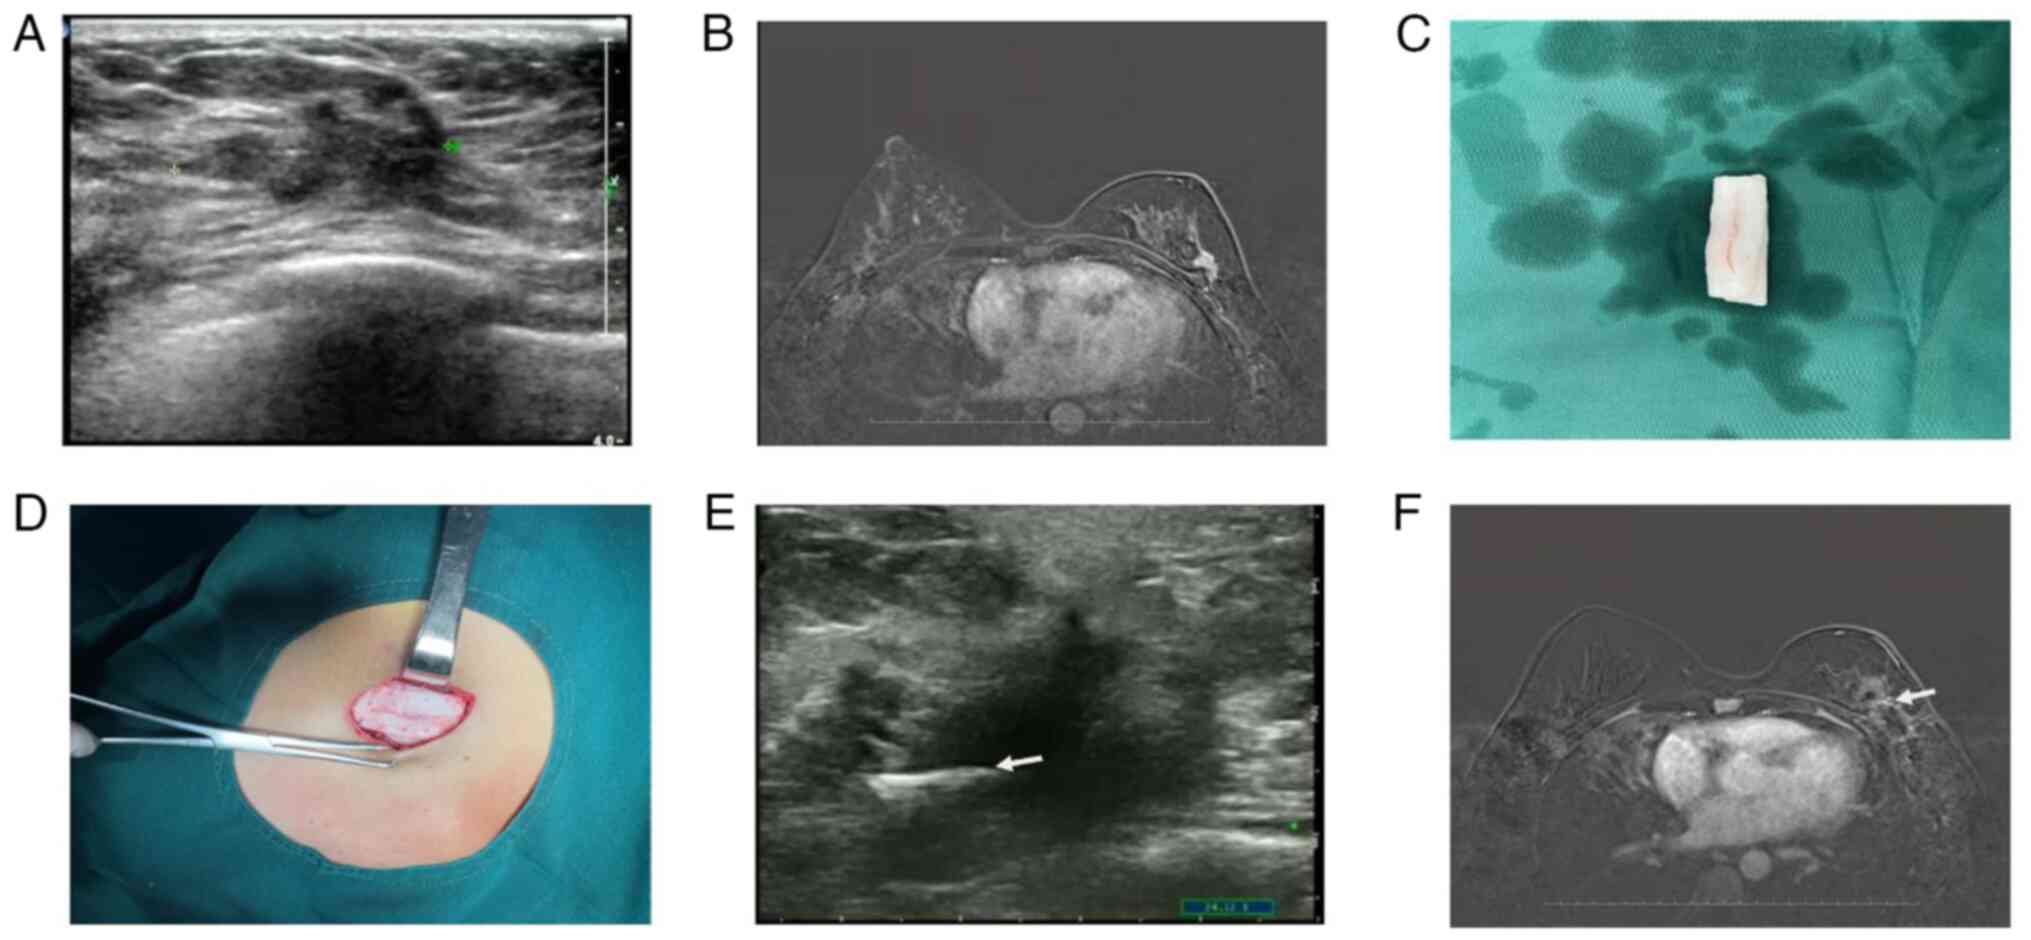

Figure 1

Preoperative and postoperative findings of patient 1. Patient 1 was diagnosed with an invasive ductal carcinoma in her right breast. (A) Ultrasonography revealed a 0.81 cm irregular mass. (B) MRI revealed a 0.9 cm abnormally enhanced signal. (C) The washed ADM was cut into 1x5 cm strips. (D) Surgical process was performed using striped ADM. The four corners of the ADM strip were fixed in the defect cavity with white silk 3-0 sutures to prevent ADM from migrating. Finally, the incision was closed using a double-layer skin closure technique. At 3 months post-radiotherapy (E) ultrasonography and (F) MRI views (ADM indicated using arrows). MRI, Magnetic resonance imaging; ADM, acellular dermal matrices.

The patient was treated with a segmental mastectomy and a sentinel node biopsy. The excised breast tissue weighed 13.4 g. Prepared ADM was fashioned into strips measuring 1 cm by 5 cm (Fig. 1C). Once a frozen section confirmed the absence of residual cancer in the margins of the excised tissue, the breast defect was filled with the prepared ADM strips. To secure the ADM in place and prevent displacement, each corner of the ADM strip was sutured using 3-0 silk sutures within the defect area (Fig. 1D). This process may take an extra 10 min compared with traditional breast-conserving surgery. Closure of the surgical site involved a two-tiered approach, with the deeper glandular tissue and the superficial skin sutured separately (12). Drainage of excess fluid was managed by a surgically placed closed drain. The incision was meticulously sutured in two layers with resorbable 3-0 and 4-0 monofilament sutures (Johnson & Johnson). Post-surgery, an elastic bandage was applied, ensuring it was not too tight to prevent compression of the reconstructed breast. Pain assessment using a visual analog scale (13) indicated an average postoperative pain level at three different times during the patient's hospitalization. The patient was released from the hospital on the third postoperative day. The final pathology report described a 0.8 cm invasive ductal carcinoma with a hormone receptor-positive profile. At 3 months post-radiotherapy, the integrity of the ADM was confirmed via ultrasound and breast MRI imaging (Fig. 1E-F). Tumor HE staining and immunohistochemical staining are shown in Fig. 2 (Department of Pathology, Tangshan People's Hospital, Tangshan City, Hebei Province, China). The patient assessed the cosmetic outcome as excellent, referencing a 4-point scale (14,15), both 3 days after surgery and 3 months post-radiotherapy (Fig. 3A-I).

A 40-year-old female patient received a diagnosis of invasive ductal carcinoma in her left breast following a core needle biopsy. Her BMI was recorded at 27.3 kg/m². Ultrasound imaging revealed a complex mass with associated smaller nodules, measuring ~2.5 cm (Fig. 4A). Additionally, a contrast-enhanced breast MRI identified an irregularly shaped mass in the upper outer quadrant of the breast (Fig. 4B).

Figure 4

Preoperative and postoperative findings of patient 2. Patient 2 was diagnosed with an invasive ductal carcinoma in her left breast. (A) Ultrasonography revealed a 2.5 cm irregular mass. (B) MRI revealed a 1.5 cm abnormally enhanced signal. (C) A hole was made every 0.5 cm on the ADM patch. (D) The ADM patch was folded into a three-dimensional grid-like structure of 1x5 cm. The four corners of the ADM three-dimensional grid structure were fixed in the defect cavity with white silk 3-0 sutures to prevent ADM from migrating. At 3 months post-radiotherapy (E) Ultrasonography and (F) MRI views (ADM indicated with arrows). MRI, Magnetic resonance imaging.

The patient underwent partial mastectomy and axillary lymph node dissection. The excised breast tissue weighed 21 g. A pattern of perforations, spaced 0.5 cm apart, was created on the ADM material (Fig. 4C). This ADM was then fashioned into a three-dimensional, grid-like construct, measuring 1x5 cm (Fig. 4C). The corners of this ADM grid were securely sutured into the surgical cavity using 3-0 white silk stitches to ensure the material remained in place (Fig. 4C). This process may take an extra 10 min compared with traditional breast-conserving surgery. Closure of the surgical site was achieved through a two-layer technique, encompassing both glandular and superficial dermal tissues (12). A closed suction drain was placed to facilitate fluid removal. The incision was meticulously closed in two layers with interrupted, dissolvable 3-0 and 4-0 monofilament sutures (Johnson & Johnson). Postoperatively, the site was dressed with a gently applied elastic bandage to support the breast structure. Pain levels, monitored by a visual analog scale, indicated an average pain score of 4 during the inpatient recovery. The patient was discharged at 3 days post-operation. Pathological analysis confirmed a 2.0 cm invasive ductal carcinoma, HR-positive, HER2-positive as the final diagnosis.

At 3 months post-radiotherapy, the three-dimensional framework of the ADM had established itself as a solid internal scaffold, with no significant structural alterations evident on ultrasound and MRI scans of the breast (Fig. 4E-F). Tumor HE staining and immunohistochemical staining are presented in Fig. 5 (Department of Pathology, Tangshan People's Hospital, Tangshan City, Hebei Province, China.). The patient assessed her surgical outcome as favorable initially, and post-radiotherapy, she reported an excellent aesthetic result, utilizing a standardized four-point evaluative scale (Fig. 6A-I).